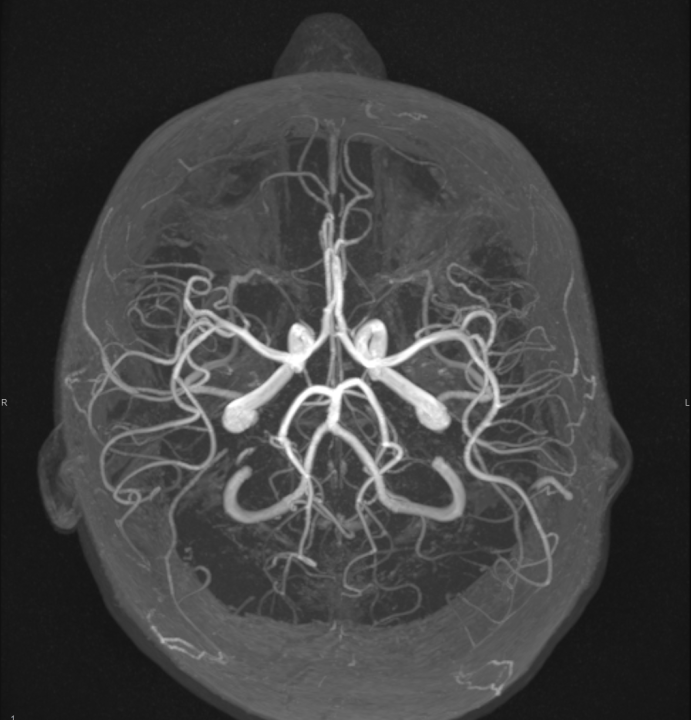

FOTO Naručite se na rendgen, ultrazvuk, CT ili MR u Poliklinici Affidea Vita!

FOTO Ako su vam potrebni specijalistički pregledi mamografija, RTG, UZV, CT i MR, koji se inače koriste za dijagnostiku velikog broja zdravstvenih problema, možete ih obaviti već danas ili sutra. Vodite računa o vašem zdravlju i zakažite pregled u Poliklinici Affidea Vita u Šibeniku na vrijeme!